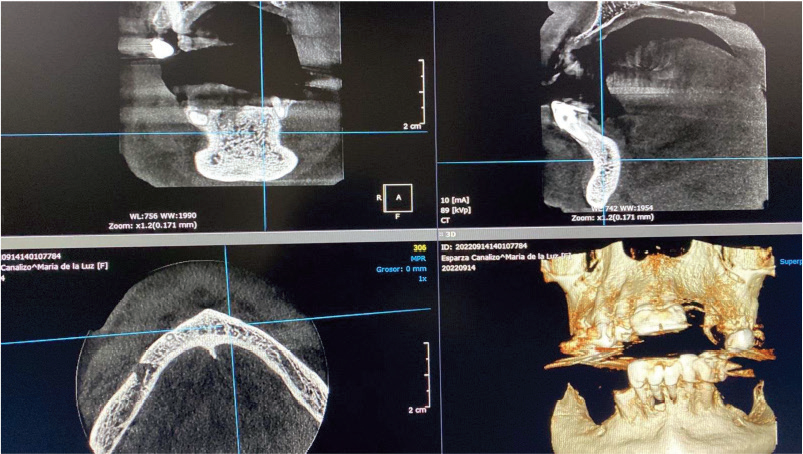

A 70 year old female patient, seemingly healthy, visited Dr. Raul Cameras Meneses’ clinic with an issue regarding her fixed prosthesis in her lower anterior teeth.

Due to the current condition of her teeth and bone structures multiple extractions were recommended, along with a surgery guide for placing five GDT Spiral Implants using the GDT surgical Kit, GDT Multi-unit Attachments on each implant, and GDT Bone Grafts (sponge grafting plug), along with a transitional prosthesis before placing the denture.